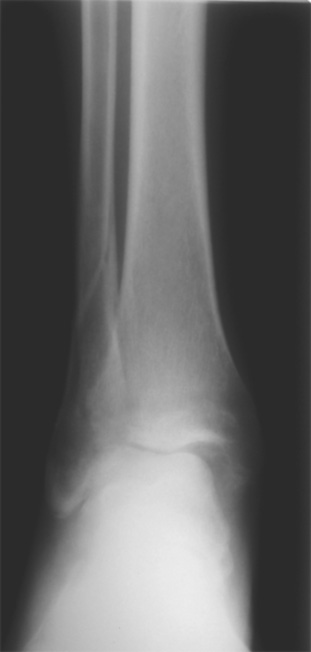

Здесь представлено решение похожей проблемы. Больной в течение года лечился консервативными мерами, и боли в голеностопе были основным показанием к операции.

Проведена обычная стандартная процедура по исправлению неудовлетворительного состояния голеностопного сустава, где кроме удлинения малоберцовой с применением compression tension device за проксимальный конец пластины, проведено замещение трикортикальным графтом из крыла, освобождение синдесмоза и медиальной щели от

фибротических масс с фиксацией.

Дополнительно у больного плоская стопа, во время операции провели небольшую скользящую остеотомию, надеемся, что поможет.